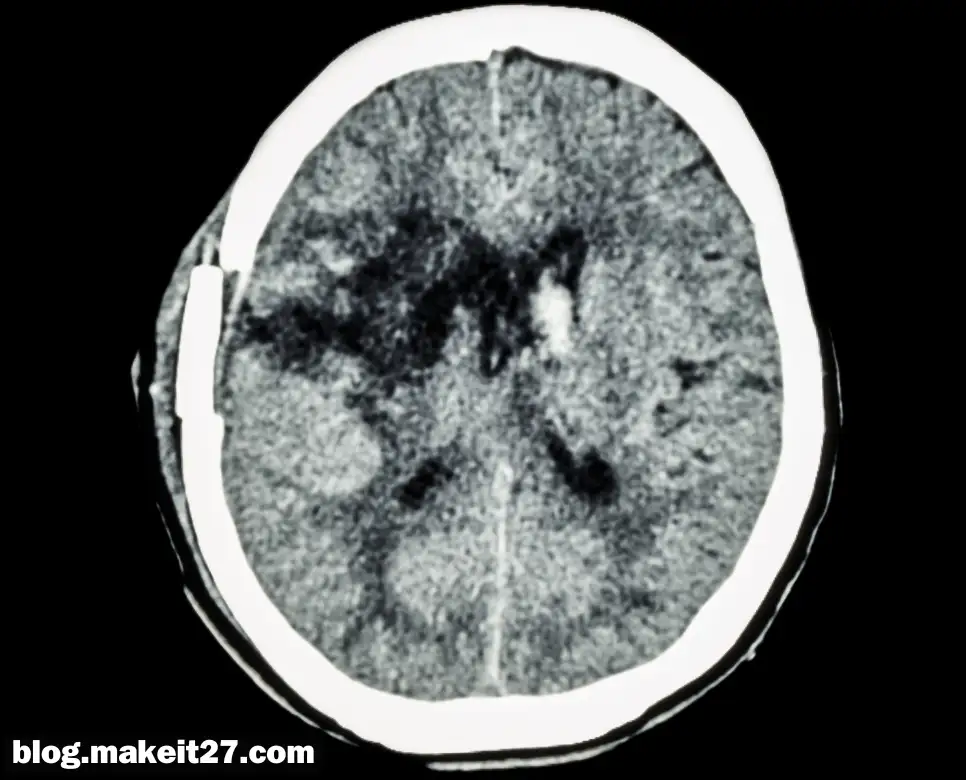

의학 용어 ‘BG’는 ‘Basal Ganglia’의 약어로, 한국어로는 ‘기저핵’이라고 합니다. 기저핵은 대뇌 변연계에 속하는 중요한 신경 구조물로, 뇌의 깊은 부분에 위치하고 있습니다. 이 구조는 운동 조절, 습관 형성, 감정, 인지 등 다양한 뇌 기능을 담당하는데 중요한 역할을 합니다.

기저핵의 손상과 질병

기저핵의 손상이나 기능 이상은 다양한 신경학적 질환을 초래할 수 있습니다. 예를 들어, 파킨슨병은 기저핵의 도파민 생성 세포가 손상되어 발생하는 대표적인 질환입니다. 이로 인해 환자는 떨림, 근육의 경직, 움직임의 느려짐 등의 증상을 겪게 됩니다.

또한, 헌팅턴병과 같은 유전적 장애도 기저핵의 손상과 관련이 있으며, 이는 운동 조절 능력의 상실과 인지 기능 저하를 가져옵니다.

기저핵과 관련된 의학 용어로는 ‘BG infarction’이 있습니다. 이는 기저핵에 혈액 공급을 담당하는 혈관이 막혀 발생하는 뇌경색을 의미합니다. 이러한 상태는 운동 능력과 인지 기능에 영향을 미칠 수 있으며, 다양한 증상을 유발할 수 있습니다.

기저핵의 손상으로 인해 나타날 수 있는 증상들은 다음과 같습니다:

- 감각 저하 또는 근육 약화

- 인지 기능의 저하

- 균형 잡기와 걷기의 어려움

- 삼킴 곤란

- 성격 변화

- 근육의 강직 또는 움직임의 제한

- 시력 손상

이러한 증상들은 손상의 범위와 정도, 침범하는 부위에 따라 다르게 나타날 수 있습니다. 때문에 정확한 진단과 적절한 치료가 필요합니다.